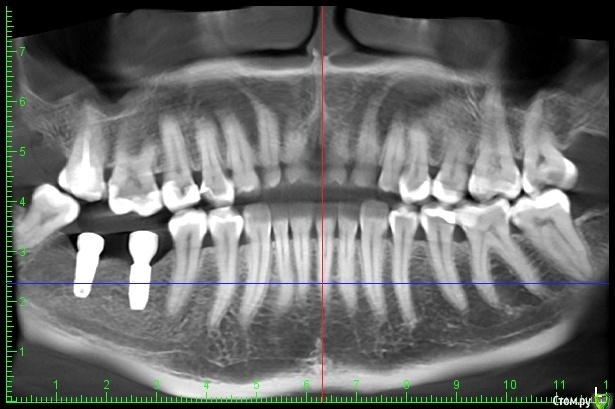

Diana1974 Опубликовано 8 января, 2021 Поделиться Опубликовано 8 января, 2021 Добрый день! Подскажите, нормально ли это и нужно ли просить что-то переделывать? 2 недели назад поставили коронки на импланты, до первого приема пищи всё было хорошо, десна выглядит нормальной, но места установки постоянно ноют, еда очень сильно набивается и также вызывает сильное давление и боль, жесткая еда и холод вызывают пульсацию. Врач сказал, всё хорошо и будет еще затягивать их. Ноющая боль появлялась еще с момента установки формирователей (в июле), но врач также говорил, что всё хорошо прижилось и идет по плану. На втором снимке стрелочкой указала сопутствующую проблему: беспричинная сильная боль и пульсация четко в десне между передними зубами, которая то утихает, то появляется вновь (стоматолог и парадонтолог осматривали, по их части проблем нет, зубы, между которыми боль ни разу не лечились и на данный момент здоровы), проблеме 3 месяца, предпринимала много чего, в итоге меня отправляют к стоматоневрологу. Всё это может быть связано с имплантами или наоборот все эти проблемы не относятся к стоматологии и нужно искать причину у невролога? Ссылка на комментарий

Diana1974 Опубликовано 9 января, 2021 Автор Поделиться Опубликовано 9 января, 2021 Попросите врача проверить все зубы вверху и внизу с этой стороны на предмет пульпита, раз вы говорите, что еще в июле появилось. Скриншоты, которые я приложила в первом сообщении взяты из кт от 23 декабря, врач тогда сказал, что мы его как раз и делаем, чтобы еще раз перепроверить все зубы, долго смотрел и сказал всё хорошо, разве что на дальнем зубе можно переделать запломбированные каналы. Ссылка на комментарий

Diana1974 Опубликовано 9 января, 2021 Автор Поделиться Опубликовано 9 января, 2021 Попросите врача проверить все зубы вверху и внизу с этой стороны на предмет пульпита, раз вы говорите, что еще в июле появилось. А по коронкам, что скажете, стоит просить что-то скорректировать, пока на них не установили постоянные пломбы? Ссылка на комментарий